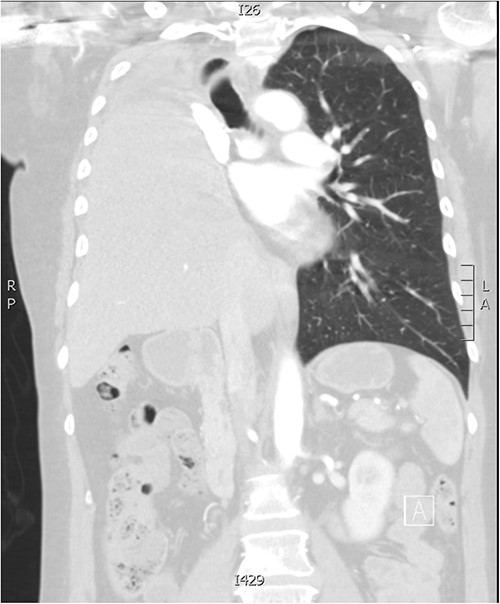

A 58-year-old female with a history of osteosarcoma arising from the right proximal humerus was initially treated with neoadjuvant chemotherapy, resection, and endoprosthetic reconstruction of the humerus, and a pedicled latissimus dorsi flap reconstruction. Four years later, a right middle lobectomy was performed for a metastasis, with histologically clear margins and no nodal involvement. Ten years following the lobectomy, she presented with a new cough. Computed tomography (CT) revealed a right hilar lobulated mass, measuring 7.1 cm × 5.6 cm × 5.9 cm, posteriorly displacing the right main bronchus (Fig. 1a and b). Positron-emission tomography showed significant uptake and an endobronchial ultrasound biopsy confirmed metastatic osteosarcoma.

(a,b) CT imaging showing a large right hilar mass with compression of right main bronchus and superior vena cava. (c) Macroscopic appearance of the right lung containing the tumour and adjacent mediastinal structures. (d) Histopathology of the metastatic osteosarcoma, demonstrating atypical spindle cell morphology.

The patient had an uneventful post-operative course and subsequently discharged home. Follow-up imaging shows complete elevation of the liver into the right thoracic cavity (Fig. 2). On review 21 years post-initial diagnosis, she remains asymptomatic and disease-free.

Follow-up CT imaging demonstrating complete migration of the liver into the right thoracic cavity.